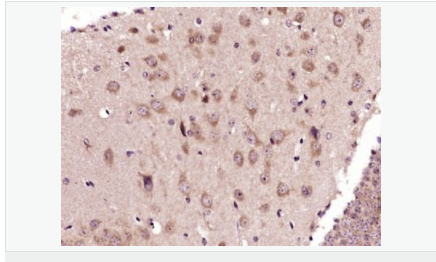

| 產(chǎn)品應用 | WB=1:500-2000 IHC-P=1:100-500 IHC-F=1:100-500 Flow-Cyt=3ug/test ICC=1:100-500 IF=1:100-500 (石蠟切片需做抗原修復) not yet tested in other applications. optimal dilutions/concentrations should be determined by the end user. |

| 產(chǎn)品介紹 | This gene encodes an adenosine receptor that is a member of the G protein-coupled receptor superfamily. This integral membrane protein stimulates adenylate cyclase activity in the presence of adenosine. This protein also interacts with netrin-1, which is involved in axon elongation. The gene is located near the Smith-Magenis syndrome region on chromosome 17. [provided by RefSeq, Jul 2008]. Function: Receptor for adenosine. The activity of this receptor is mediated by G proteins which activate adenylyl cyclase. Subcellular Location: Cell membrane; Multi-pass membrane protein. Similarity: Belongs to the G-protein coupled receptor 1 family. SWISS: P29275 Gene ID: 136 Database links: Entrez Gene: 136 Human Omim: 600446 Human SwissProt: P29275 Human Unigene: 167046 Human Important Note: This product as supplied is intended for research use only, not for use in human, therapeutic or diagnostic applications. |